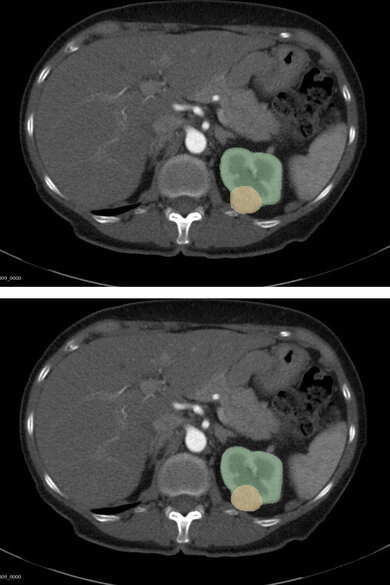

Voorbeeld: de AI-voorspelling (boven) en de door artsen ingetekende ‘ground truth’ (onder) van dezelfde nierscan overlappen volledig. Het model herkent het gezonde nierweefsel (groen) en de tumor (geel) precies zoals een arts dat deed. De AI had de scan niet eerder gezien. Beeld: TUe.